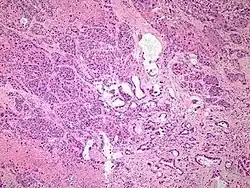

| Micrograph of an adenosquamous carcinoma of the lung. The adeno- or glandular component is on the left of the image and the squamous component on the right of the image. H&E stain. | |

Light microscopy shows a combination of gland-like cells and squamous epithelial cells.[4] On immunohistochemistry, it is typically positive for CK5/6, CK7 and p63, and negative for CK20, p16 and p53. On genetic testing, KRAS and p53 are typically altered.[4]